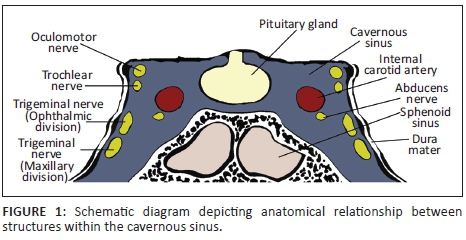

The cavernous sinuses (CS) are paired dural venous sinuses that form part of a complex network of venous channels into which the superficial venous system of the head drains. It receives venous blood from the superior and inferior ophthalmic veins, Sylvian veins and pterygoid venous plexus and in turn empties into the superior and inferior petrosal sinuses which ultimately drain via the internal jugular vein. Because of its location in the parasellar region, many neurovascular structures (including the internal carotid artery [ICA]) traverse the sinus providing an opportunity for complex interactions to occur between the structures (see Figures 1 and 2).

The ICA has a tortuous path and is divided into segments. After passing through the superior part of the foramen lacerum to enter the cranial cavity, the ICA reaches the petroclinoid ligament where it passes anteriorly between the layers of the dura that form the CS taking up a medial position within the sinus. The ICA then exits the CS in the region of the anterior clinoid process. Branches of the ICA arising within the CS are the meningohypophyseal artery (MHA), inferolateral trunk (ILT) and capsular artery which in turn give off sub-branches supplying the dural covering of the CS. The medial wall of the CS is supplied by branches of the MHA and capsular arteries whilst the inferior and lateral walls are supplied by the ILT. The ICA's companion branch, the external carotid artery (ECA), whilst supplying the major structures of the head and neck, also supplies parts of the meningeal layers in the cavernous region of the brain via distal sub-branches such as the middle meningeal artery which anastomose with distal branches of the ILT.